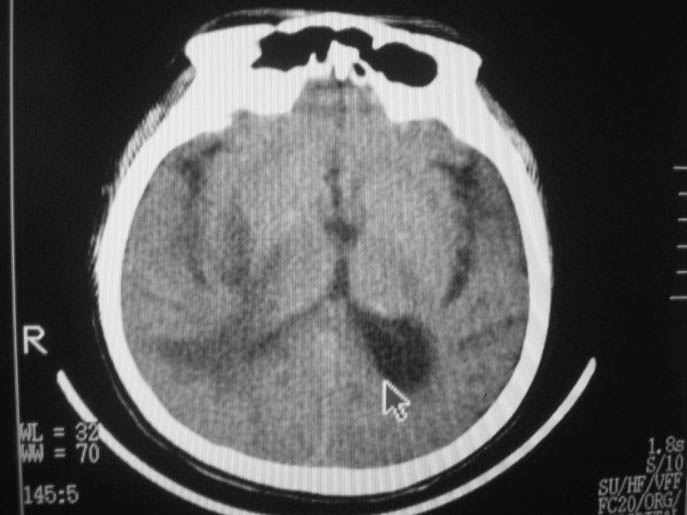

以下是引用卜一在2009-9-7 16:23:00的发言:[br]支持:胶质瘤伴出血!

以下是引用随光逐影在2009-9-8 7:40:00的发言:[br]考虑脑转移瘤或胶质瘤并肿瘤卒中;建议行ct增强扫描检查。

以下是引用熊熊在2009-9-7 18:31:00的发言:[br]胶质瘤伴出血[br]建议增强